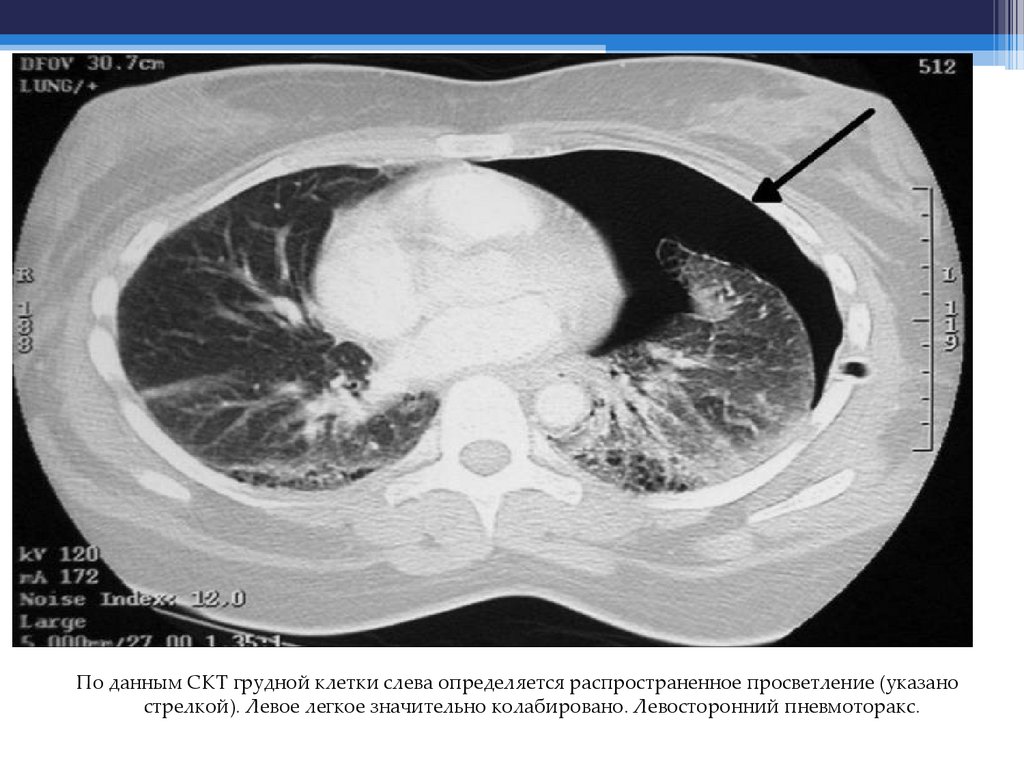

9. Пневмоторакс

По данным СКТ грудной клетки слева определяется распространенное просветление (указано

стрелкой). Левое легкое значительно колабировано. Левосторонний пневмоторакс.